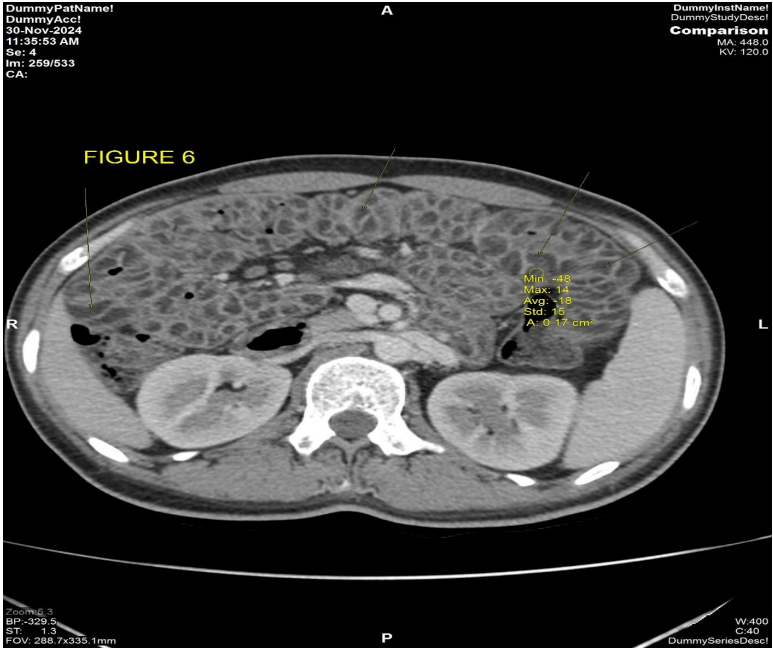

Response scan was done on 10/2024 (Fig 6) which showed mild interval decrease in the size and increase in necrosis of the right lumbar region lesion, with no other symptoms, show continued on pazopanib.

Patient complaint of abdominal pain with diarrhea and weight loss since 1 month, so a CECT thorax abdomen pelvis (Fig 6) was performed on 30/11/2024, which showed no interval change in the size and necrosis of the right lumbar region lesion, however there was new onset significant bowel wall thickening with submucosal fat deposition (-18 HU) mild luminal narrowing involving the entire jejunum with maximum thickness of 15 mm. [4]

Figure 6: CECT abdomen dated 30/11/2024 axial post contrast view shows diffuse circumferential bowel wall thickening with submucosal fat is seen involving the jejunal wall with HU of -13, consistent with fat.

Figure 6